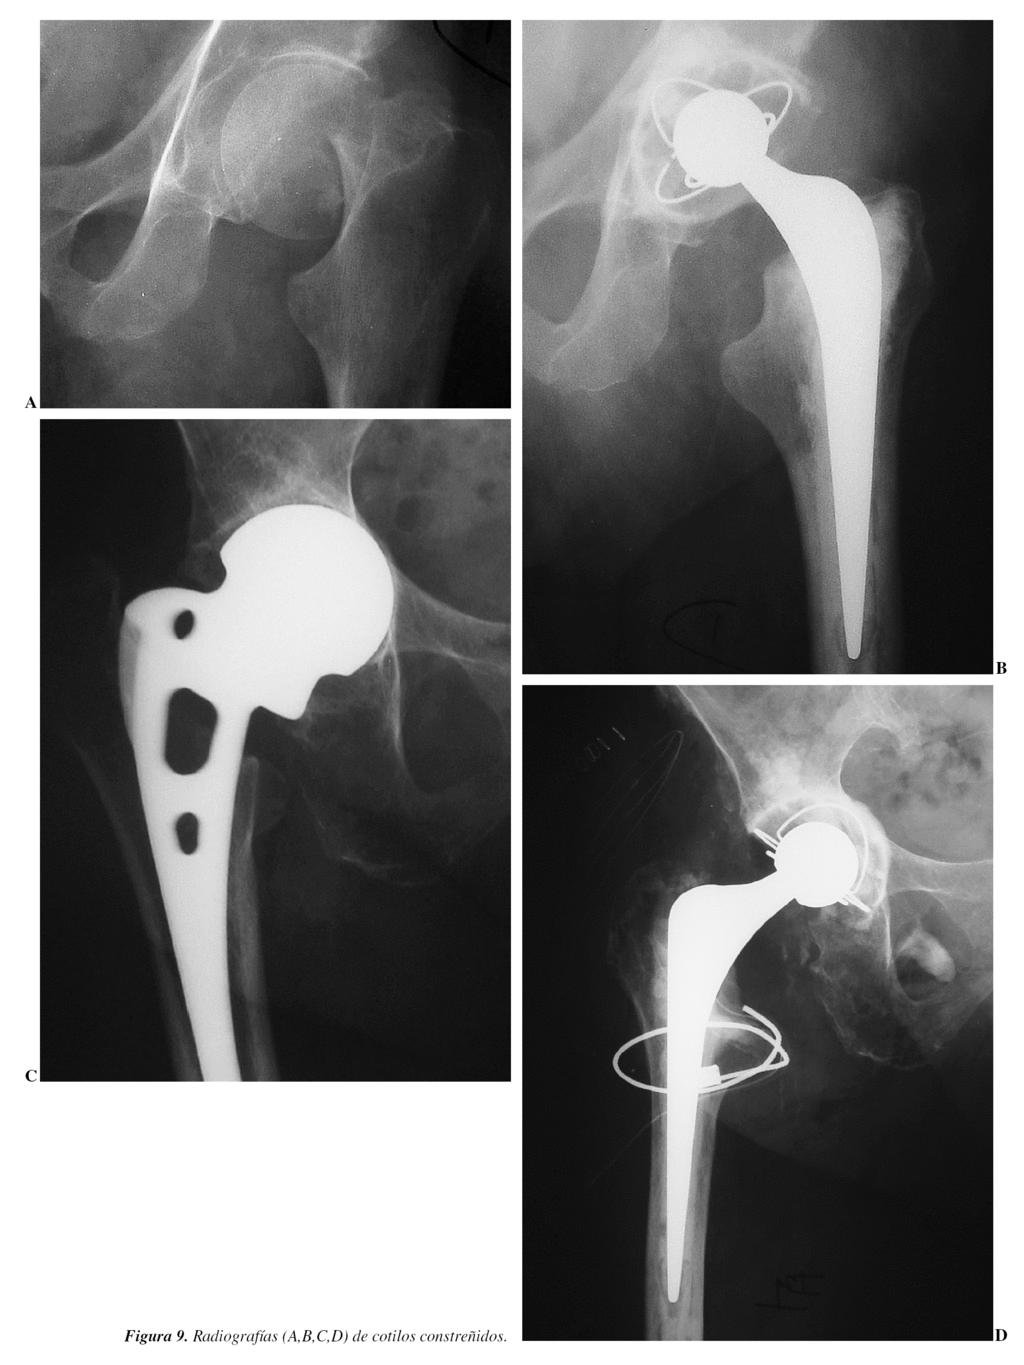

Conversión a cotilo constreñido o con mecanismo de bloqueo

Estos implantes que capturan la cabeza femoral proporcionan una estabilidad que permite resolver muchos de los problemas que hasta ahora eran intratables. Hay una gran variabilidad en el diseño de estos implantes constreñidos, que a la vez proporcionan distintos grados de constricción, y que además están sujetos a distintas formas de fallo. En general hay tres tipos principales de implantes constreñidos: cotilos que reciben en su interior más de la mitad de la cabeza (ecuador) y que emiten un chasquido cuando la capturan, otros en que la constricción la proporciona un anillo metálico alrededor de la periferia de un inserto de polietileno y los implantes constreñidos tripolares.

Los primeros se caracterizan además porque la cabeza protésica se encuentra más penetrada de lo normal y por consiguiente, al no disponer de ningún mecanismo de estrangulación, son los que determinan menor constricción (figs. 8, 9 y 10).

Las publicaciones refieren porcentajes entre el 67 y el 96% de resultados favorables.

Resultados

Goetz et al32 reportan 53 caderas (tripular constreñido) con más del 90% de buenos resultados a dos años.

Anderson, Murray y Skinner33 comunican 18 caderas (cotilo constreñido con mecanismo de bloqueo) con un 67% de resultados favorables.

Los fracasos posibles se pueden presentar en cualquiera de las tres intercaras: a) inserto-cotilo metálico; b) cabeza-inserto y c) mecanismo de bloqueo.

En contra

No todos los cotilos constreñidos proporcionan igual cantidad de constricción.

El rango de movilidad de la mayoría de los cotilos constreñidos, antes del choque entre el cuello y el inserto, es pequeño.

Se produce un aumento del desgaste del polietileno.

Una complicación no frecuente es la disociación cono-cabeza, siendo necesaria la reducción abierta y aumentar la longitud del cuello con o sin faldón (fig. 11).

Existe la posibilidad de fracaso en las dos intercaras entre el cotilo metálico y el hueso y entre el cotilo metálico y el inserto debido a la transmisión de cargas excesivas a estas dos intercaras.

Habitualmente, si la cadera se vuelve a luxar, al quedar la cabeza aprisionada y constreñida o fuera del inserto, es necesaria la cirugía abierta, aunque tenemos dos casos en los que se ha podido evitar la cirugía, siendo favorable la reducción cerrada.